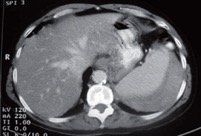

Subsequently he was doing well. After 5 days, he suddenly developed left upper abdominal pain, sweating and lethargy. He was immediately wheeled to the ICU and resuscitated with fluids, blood and blood products. The Hb dropped to 7.2 g/dl, and he had BP of 90/60mm Hg, he was tachypneic and pulse rate was 104/ min. The patient was planned for CT proceed and emergency exploratory laparotomy.

Splenectomy was done. The patient was gradually weaned off from the ventilator and Hb improved up to 9.6g/dl by fresh blood transfusion. He was transferred to room on POD 4 and was started on oral diet subsequently. Then on POD 7, he was discharged and was prescribed polyvalent pneumococcal vaccine at review.